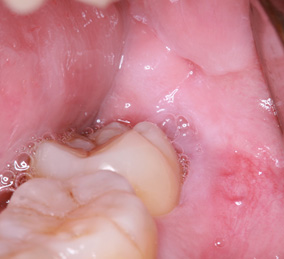

3日目:歯牙移植術を行います。

抜歯する歯の周囲に麻酔をします。

傷んだ歯を抜歯します。

親しらずを抜歯して、移植します。

歯の固定や傷口を縫合します。